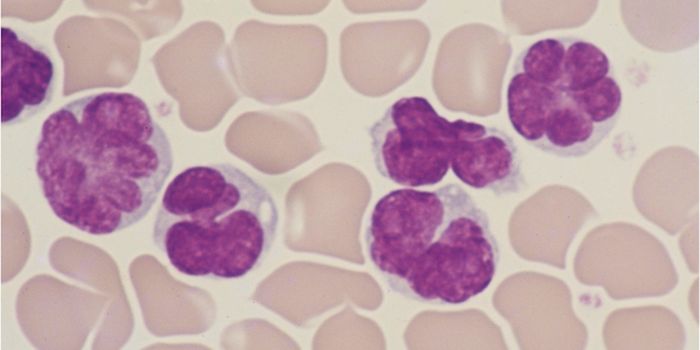

MAR 30, 2022Clinical & Molecular DXStrategies to Improve Your Lab’s Blood Culture Process A blood culture is a routine laboratory test in which blood ...